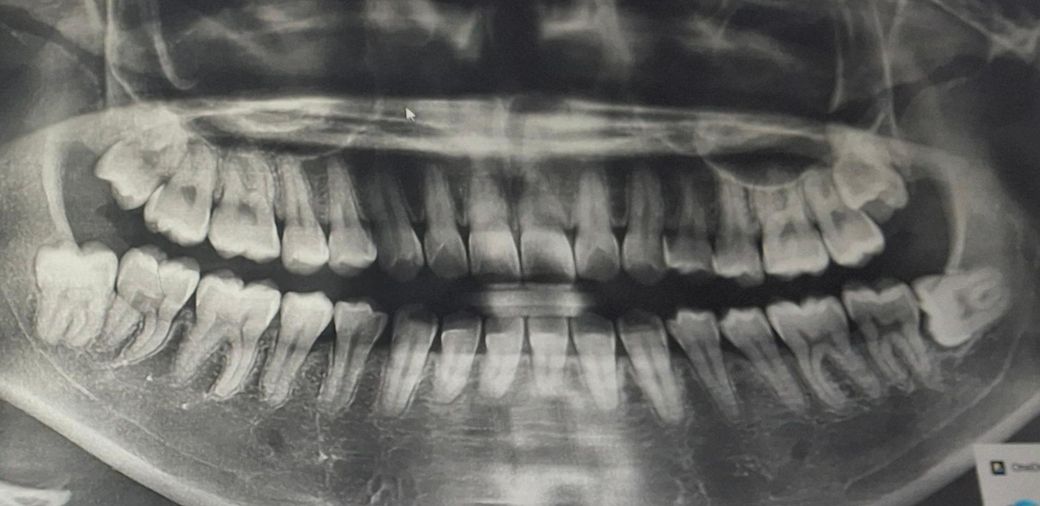

사랑니 발치할 때 한꺼번에 2개 발치하나요

현재 좌측의 아래 잇몸이 아프고 입이 벌려지지 않아서 치과를 갔더니 윗쪽의 사랑니가 문제라 이걸 발치해야 될 것 같다고 하시더라구요. 근데 아래 사랑니도 뽑아야된다고 하시는데 한꺼번에 위아래 두 개 발치해도 괜찮을까요? 아니면 보통 따로 발치하나요?

• 1번 째 사진

편측으로 위아래 사랑니는 같이 발치 할수 있습니다.

같은쪽의 위,아래 사랑니는 환자가 원한다면 하루에 뽑을 수도 있습니다 다만 사랑니 발치 난이도가 높아서 시간이 오래 걸릴 것으로 보이면 하루에 하나씩 뽑는 경우도 있습니다